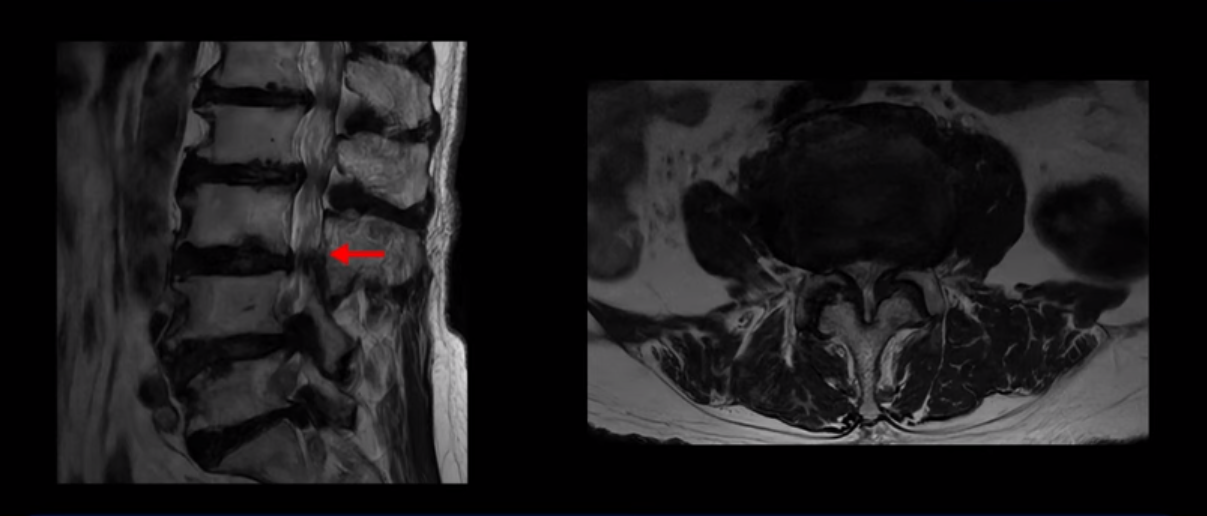

이 환자분은 MRI로 보면 허리 여러 마디가 신경이 매우 심하게 눌려 보이는 분입니다. 이분 MRI를 보면서 간단히 설명해 드린 후 어떻게 이렇게 신경이 심하게 눌린 환자분이 수술 없이 근육신경재활치료로 좋아질 수 있는지, 다리가 아파 걷지 못하는 환자가 어떻게 안 아프고 잘 걸을 수 있게 되는지, 10년 동안 괴로웠던 양 발의 시린 증상은 어떻게 사라질 수 있는지, 치료는 어떻게 하는지 자세히 설명 드리겠습니다.

MRI 보시면 (2-8) 허리의 5마디가 전부 다 심하게 퇴행되어 있습니다.

5마디 전부 다 심한 중심성 협착이 있습니다.

4번 5번,

5번 6번

이렇게 모두 다 심하게 막히는 경우는 드문데요. 또한 오른쪽, 왼쪽 신경이 빠져나가는 추간공도 다 심하게 막혀있습니다.

오른쪽, 왼쪽 이렇게 신경 구멍들이 다 좁아지고 신경이 눌리니까 양쪽 다리가 발바닥까지 아파서 걷기 어렵고 양쪽 발이 10년 넘게 시린 겁니다. 당연히 수술해서 눌린 신경을 풀어줘야 한다고 들으셨는데요. 이런 환자분을 어떻게 수술 없이 치료할까요? 지금부터 설명해 드립니다.

이분 신경이 눌리는 증상은 오래됐지만, 증상이 아주 심해진 건 올해 들어와서입니다. 그럼, 이분 MRI 영상도 이렇게 심하게 안 좋아진 게 올해 들어와서일까요? 이분의 MRI로 보이는 협착은 아주 오래된 겁니다. 그래서 신경 구멍이 심하게 좁아진 것도 올해가 아니고 오래된 겁니다. 작년, 재작년에 훨씬 덜 아팠을 때 MRI를 찍었어도 신경 구멍 좁은 정도는 별반 차이가 없었을 겁니다.

실제로 수많은 논문에서 70세 이후 MRI로 협착이 보여도 아프지 않은 무증상 협착이 많다고 설명합니다. 협착이 있어도 안 아픈 사람들이 많다는데, 이게 왜 그럴까요? 근육 기능이 정상적이고 좋은 사람들은 근육이 허리를 잘 지지해 주니까 협착이 있어도 신경이 덜 눌리거나 안 눌리는 겁니다. 즉 근육이 좋으면 신경이 덜 눌리고 근육이 좋아지면 협착증이 좋아지는 겁니다. 그래서 저희가 근육 재활치료를 통해 근육의 기능을 회복시키면서 동시에 신경의 기능을 회복시키는 치료를 하는 겁니다. 이런 분들이 근육 재활치료를 통해서 협착증 증상이 좋아진다면 이런 분들의 협착증도 아프지 않은 무증상 협착으로 바뀌게 되는 겁니다.